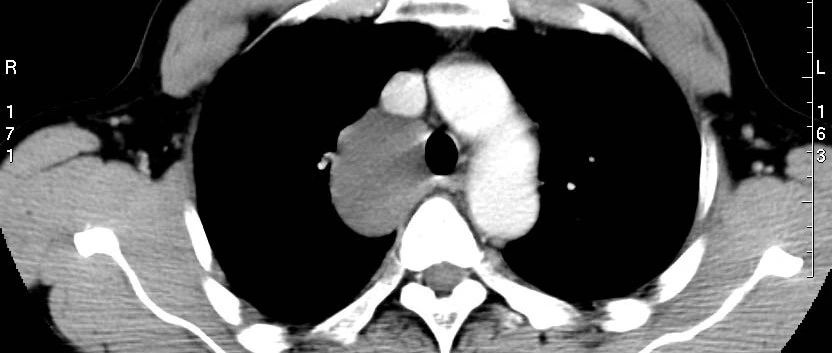

*仅供医学专业人士阅读参考这个病你能想到吗?病例简介患者中年女性,规律维持性腹膜透析7年余,反复关节疼痛伴胸闷、气促1年余。既往史:既往有"癫痫"病史10余年,混合痔病史1年余,多次骨折病史。体格检查:体温:36.5℃ 脉搏:84次/分 呼吸:20次/分 血压:174/105mmhg神志清楚,慢性病容,贫血貌,双肺呼吸音粗,双下肺可以闻及少量湿性啰音。心率84次/分,心律齐,各瓣膜区无杂音。腹部平坦,腹壁柔软,无压痛,无反跳痛。Murphy征阴性,肝脏、脾脏未触及,移动性浊音阴性,双侧肾区无叩痛,肠鸣音正常,4次/分,双侧下肢重度凹陷性浮肿。...